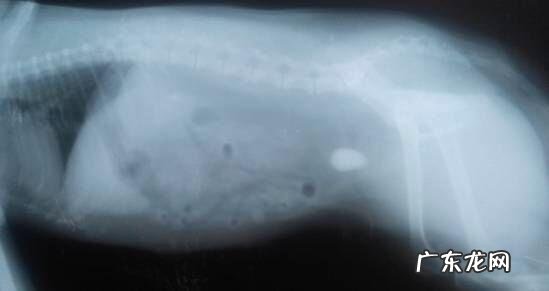

文章插图

X光下,另一个病案中膀光内尿结石 。